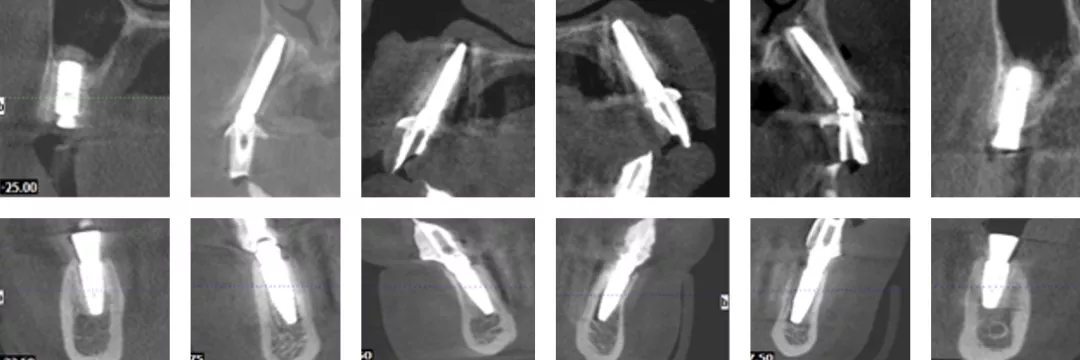

· 术后CBCT检查可见种植体植入位置佳,与术前设计一致。

· 植入精度分析,误差较小。

· 上下各计划植入6颗种植体。其中14、24种植体倾斜植入,15、25经牙槽嵴顶上颌窦提升植骨,其余牙位无需植骨。

种植体位置设计,可见上前牙唇侧骨量过丰满,需适量去骨。同时上下颌均需要截骨处理。